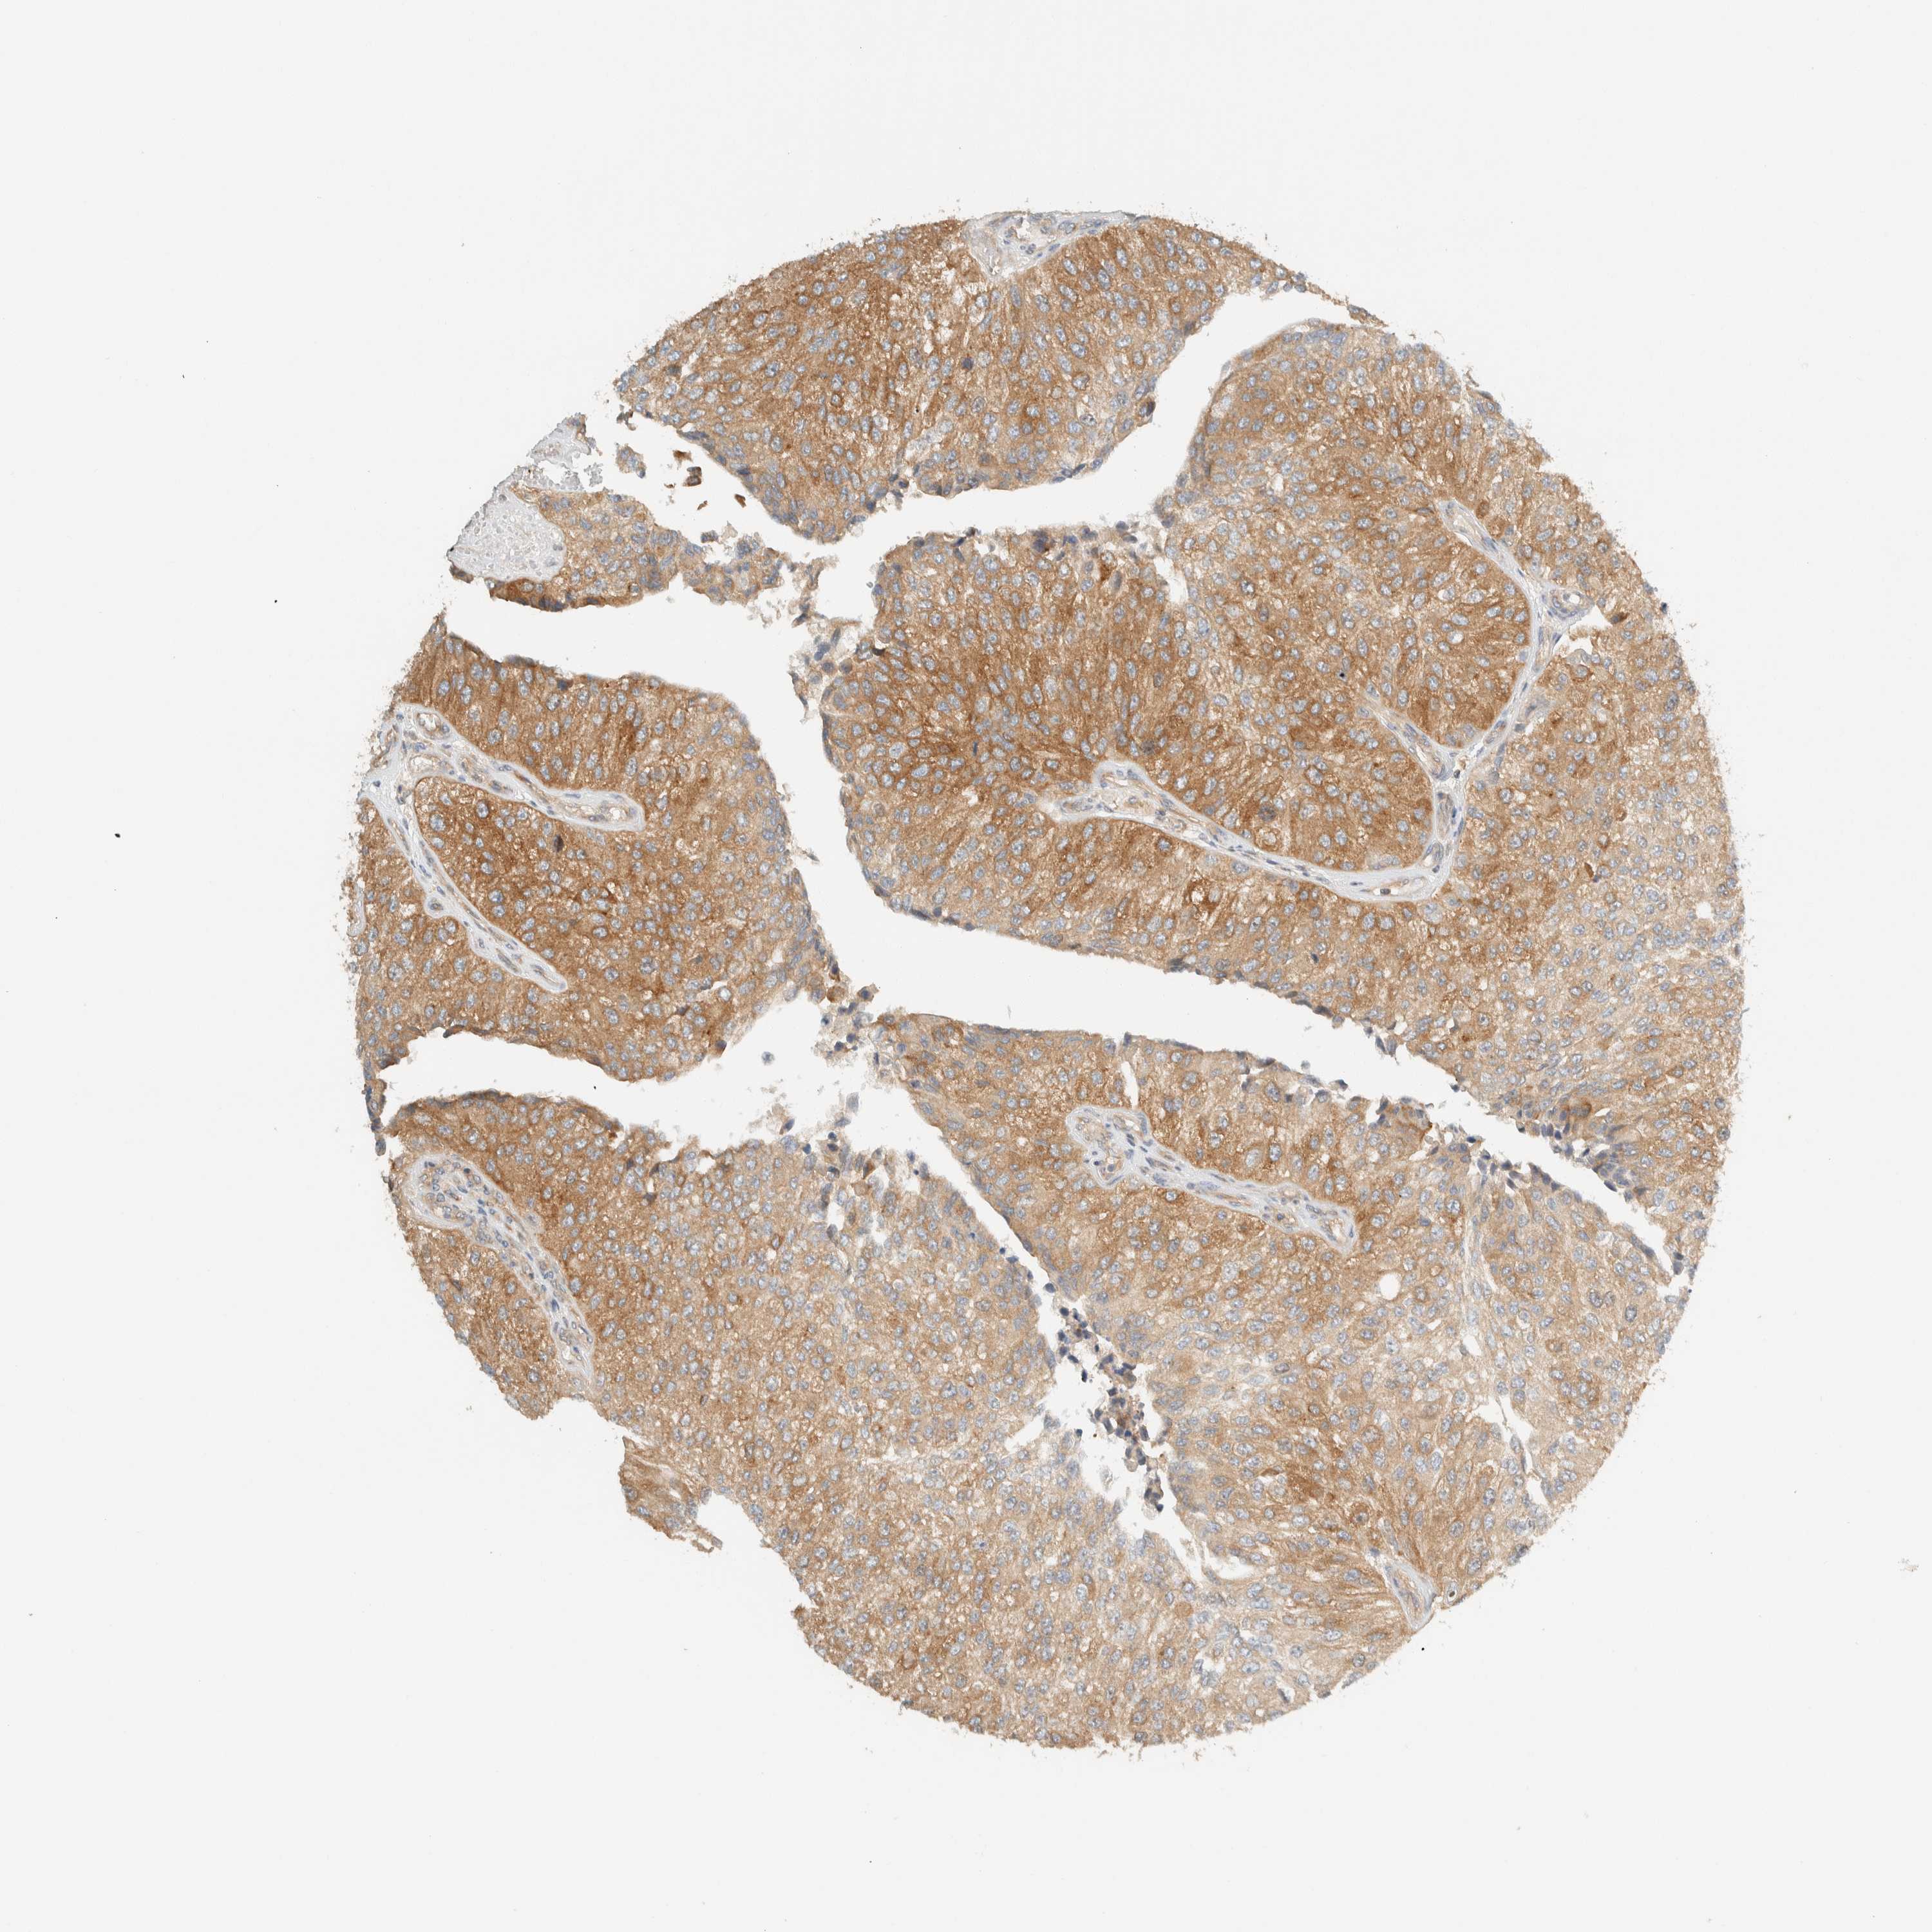

UROTHELIAL CANCER - Protein expressioni

A mouse-over function shows sample information and annotation data. Click on an image to view it in a full screen mode. Samples can be filtered based on level of antibody staining by selecting one or several of the following categories: high, medium, low and not detected. The assay and annotation is described here.

Antibody stainingi

Antibody staining in the annotated cell types in the current human tissue is reported as not detected, low, medium, or high, based on conventional immunohistochemistry profiling in selected tissues. This score is based on the combination of the staining intensity and fraction of stained cells.

Each image is clickable and will lead to virtual microscopy that enables deeper exploration of all samples and also displays staining intensity scores, fraction scores and subcellular localization as well as patient and tissue information for each sample.

Antibody HPA023399

Antibody HPA023822

Staining

High

Medium

Low

Not detected

Intensity

Strong

Moderate

Weak

Negative

Quantity

>75%

75%-25%

<25%

None

Location

Nuclear

Cytoplasmic/membranous

Cytoplasmic/membranous,nuclear

Urothelial carcinoma, Low grade

Urothelial carcinoma, High grade